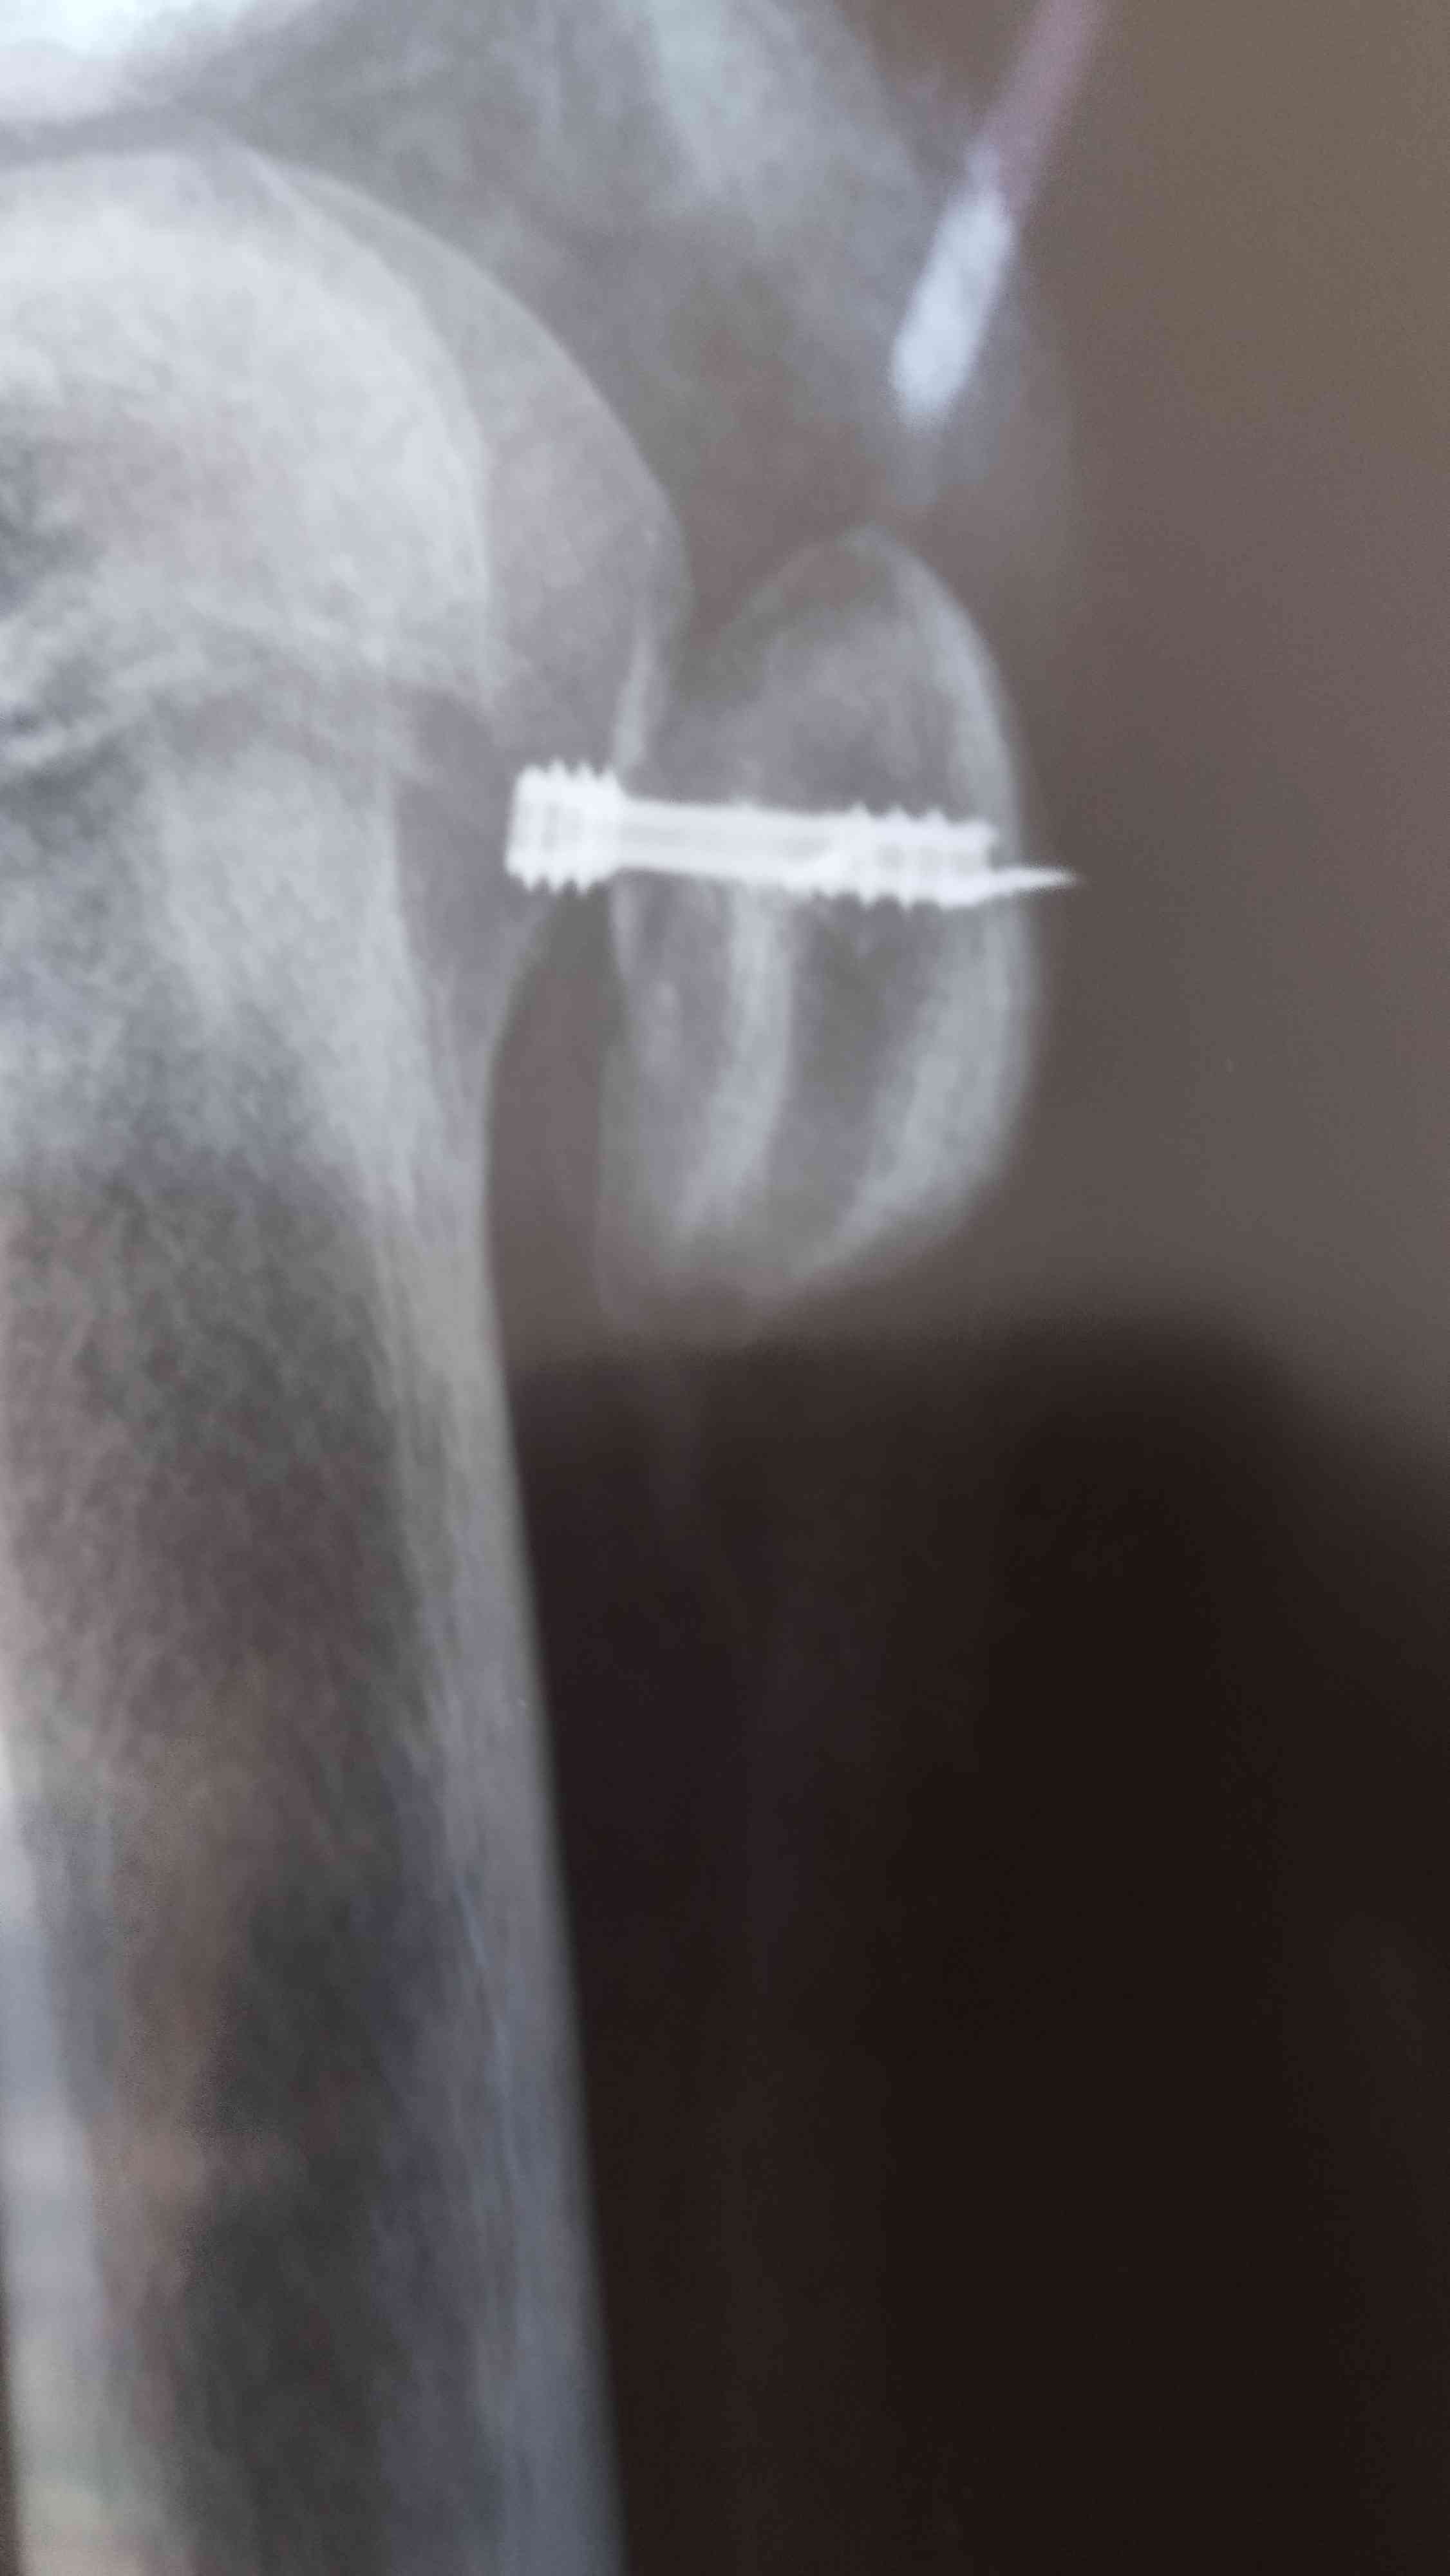

د. محمد الشوليتحتاج لعمل عملية بالمنظار الجراحي للكتف لإصلاح الخلع التكرر بالكتف وإصلاح غضروف المفصل لمنع الخلع وذلك بواسطة خطاطيف